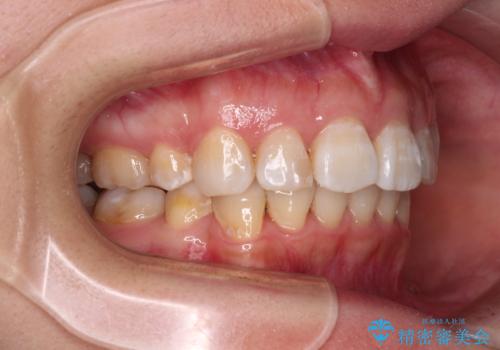

飛び出した前歯を引っ込めたい 目立たないワイヤーでの抜歯矯正

口元を積極的に引っ込めるために、上下左右の小臼歯計4本を抜歯することとしました。

矯正治療終了近くに九州へ引っ越すことになってしまい、なかなか来院することができなくなったため、引っ越してから1年以上の期間が必要となってしまいました。